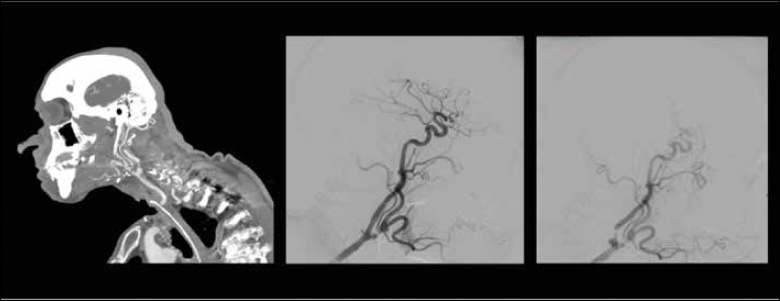

Neurovascular intervention was the preferred treatment in 92% (n = 47) of events. Among the 67% (n = 34) treated with an embolisation procedure, 26% (n = 13) included insertion of a stent for revascularization. Figures 1 and 2 describe two specific occurrences of an imminent carotid blowout and the neurovascular intervention adopted.

Figure 2. Shows sagittal CT and CTA images of a 64-year-old male revealing an aneurysm in the left internal carotid artery with peristomal bleeding. Post-treatment images demonstrate the successful placement of a stent, which bypasses the affected ICA segment, controlling the source of hemorrhage.